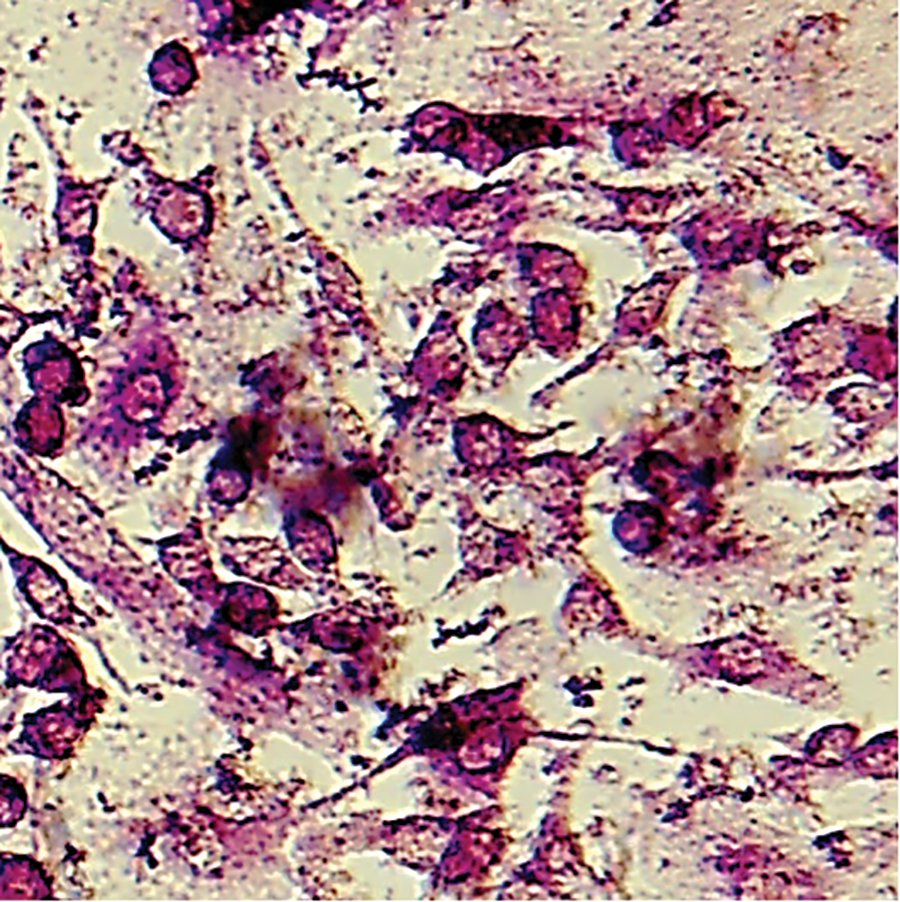

Staining of the Tartrate-Resistant Acid Phosphatase in Osteoclasts

The osteoclasts derived from the bone marrow cells were evaluated by the Staining Kit purchased from the Kamiya Biomedical Company (Seattle, WA, USA). Briefly, the culture medium was removed, and each well was washed with 100 μL of phosphate buffer solution (PBS). Then, 50 μL of fixative was added to each well for 5 minutes. Each well was washed with dH2O, followed by the addition of 50 μL of chromogenic substrate to each well and incubation for 20 to 60 minutes. Then, an inverted microscope was used, and each well was photographed with a digital camera (Motic AE200, USA). The osteoclasts were identified by the red colour that was developed and quantified by tartrate-resistant acid phosphatase (TRAP) staining using Imaged/Fiji 1.46 software (NIH, USA) Fig. 1.

Fig. 1. Osteoclasts that are derived from bone marrow cells.

Murine calvarial osteoblasts and bone marrow-derived osteoclasts in monolayer cultures constitutively synthesized IL-1β, TNF-α, and RANKL from 0 to 96 hours. At 0, 24, 48 and 72 hours after a 20-minute stimulation with the micropulse vibration instrument. The black bars represent control cells, and the white bars represent micropulse-treated cells, the culture medium were analysed by ELISA. The results are expressed as the mean ± SEM for 5 cultures (Fig. 2). IL-1β was significantly upregulated in osteoblast cultures (Fig. 2B, Table I) and significantly downregulated in osteoclast cultures (Fig. 2A, Table I). TNF-α expression in osteoblasts was significantly upregulated from 0 to 96 hours (Fig. 2D, Table II) and downregulated in osteoclast supernatant from 0 to 48 hours (Fig. 2C, Table II), and sRANKL expression was significantly downregulated in osteoblasts from 0 to 72 hours (Fig. 2F, Table III) and in osteoclasts from 0 to 96 hours (Fig. 2E, Table III). Bone marrow-derived cells in monolayer cultures were analysed for TRAP (Fig. 1), and the number of cells with positive staining developed different intensities of red colour. Mouse bone marrow cultures were stimulated for 20 minutes per day for 0 to 72 hours with the AcceleDent instrument and showed significant upregulation of CatK expression from 0 to 72 hours compared with that in the control group (Figs. 3 and 4, Table IV).